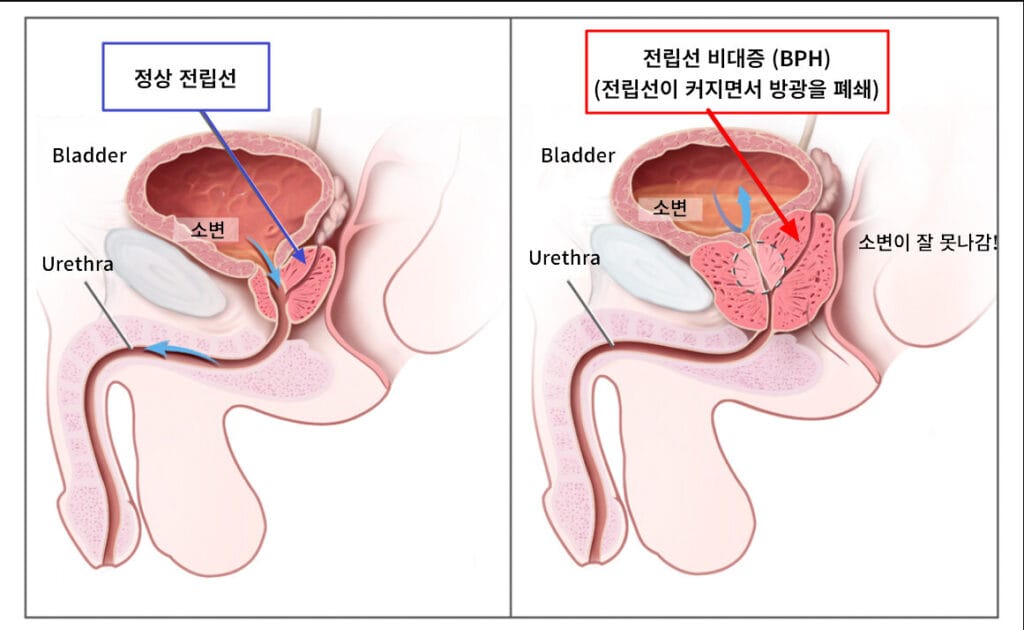

양성 전립선 비대증(BPH)은 전립선이 비정상적으로 커져서 요도를 압박하고 배뇨 증상을 유발하는 남성의 흔한 비종양성 질환입니다.

요도 주변의 전립선 Transitional Zone이 과형성되면서 배뇨 지연, 빈뇨, 약한 요줄기 등 하부요로증상을 유발합니다.

| ㅍ 비종양성 전립선세포 과형성에 의해 요도가 압박되어 배뇨장애가 발생합니다. |